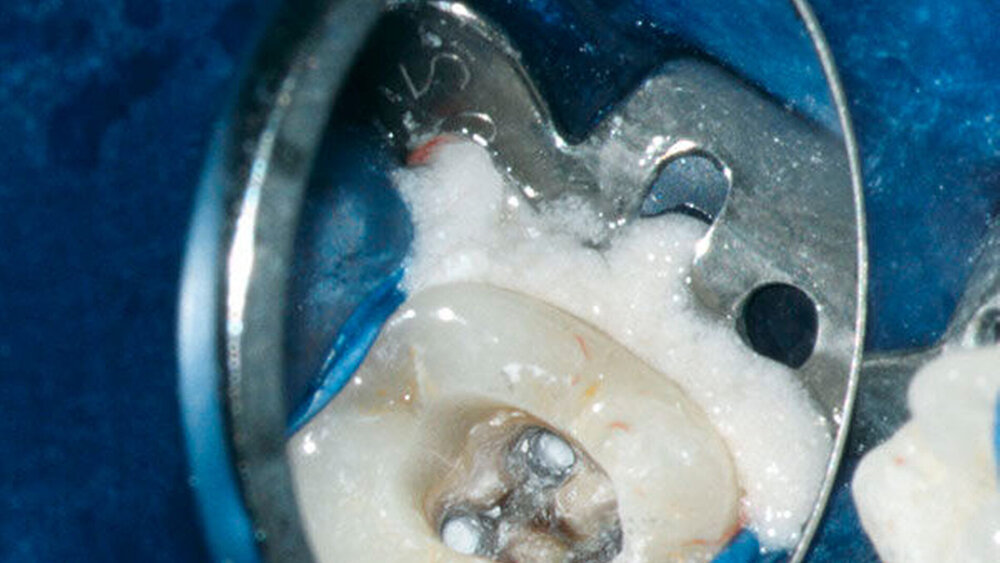

In der ersten Therapiesitzung erfolgte – nach Isolierung mit Kofferdam – die Trepanation des Zahnes und die Stiftentfernung mit Ultraschallinstrumenten. Im Anschluss wurden die drei gefüllten Kanäle revidiert, der vierte, nicht abgefüllte, mesiobukkale Kanal dargestellt und präpariert. Die elektronische Längenmessung ergab 14,5 mm für den mesiobukkalen Kanal, 17,0 mm für den mesiolingualen, 15 mm für den distobukkalen und 16 mm für den distolingualen. Aufgrund der großen initialen Kanaldurchmesser und der guten Einsicht bis ins periapikale Gewebe (Abbildung 2) wurde auf eine Längenmessaufnahme verzichtet. Die Desinfektion erfolgte mit Natriumhypochlorid (NaOCl) 5 Prozent und EDTA 17 Prozent, sowie Schallaktivierung mittels EDDY-Spitzen (VDW, München). Das Wurzelkanalsystems wurde manuell mit K-Feilen bis IS0 70 präpariert. Es folgte eine medikamentöse Einlage mit AH Temp (DentsplySirona, Bensheim). Danach wurde eine Aufnahme zur Kontrolle der vollständigen Guttapercha-Entfernung und der suffizienten Einbringtiefe des Kalziumhydroxids angefertigt (Abbildung 3).